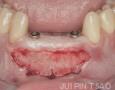

Surgery

1 Months